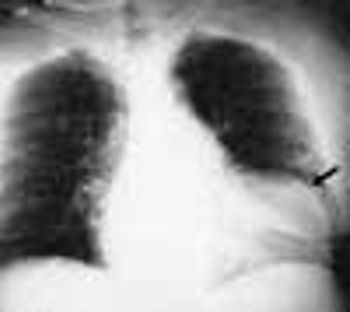

Ten days before presenting for evaluation, a 69-year-old man began to experience neuralgic pain and noticed the eruption of painful erythematous macules and papules on the right side of his chest. Within 24 to 72 hours, vesicles and pustules arose at the site. One week after onset, several of the lesions dried and crusted.